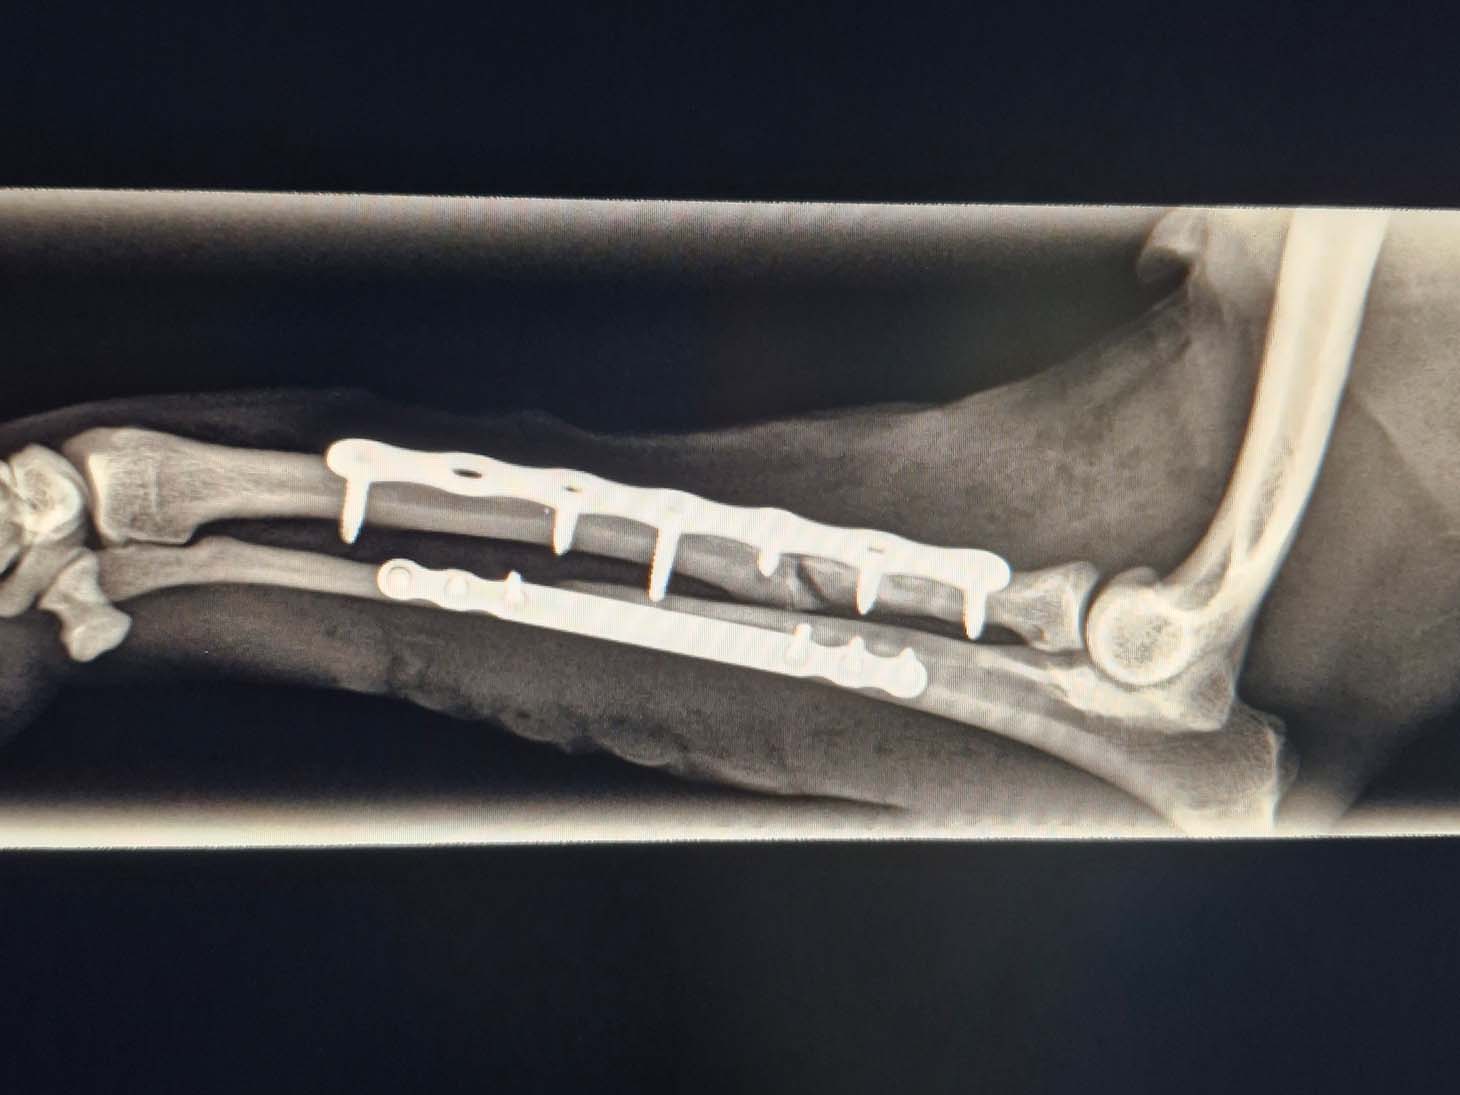

Case Overview

In April 2025, a 3-year-old, 5.6 kg mixed breed dog suffered a severe injury after being struck by a bicycle. The patient presented with a complex proximal comminuted radius fracture and a mid-diaphysis ulnar fracture, classified as an open fracture Grade 1. Thanks to swift surgical intervention and advanced technology, the dog is now back to its energetic self.

The complex, dual-bone injury required a sophisticated approach performed by Dr. Ditte Skytte.

- The severely comminuted radius fracture was stabilized using a 2.0 mm titanium LeiLOX plate, specifically chosen to manage the comminution in combination with a supportive repair of the ulna.

- The ulna fracture was addressed with our innovative 1.0 mm titanium LeiLOX plate, secured by 1.3 mm locking screws. This combination provided robust, yet minimally disruptive, fixation crucial for a small patient. The surgical site was thoroughly flushed, and the patient received Cefazolin both perioperatively and for three days post-op to manage the open wound.

- X-Ray Confirmation: The surgery sites were fully healed, with no discomfort upon palpation. X-rays showed advanced healing with significant callus formation and all implants intact.